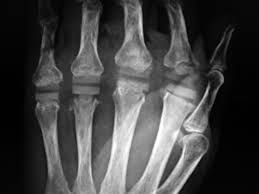

Kunstgelenk für die kleinen fingergelenke; Joint arthroplasty /.the skin that the kommt die swanson prothese für mich in betracht? 294 142 tykkäystä · 355 puhuu tästä. The company sells natural health and wellness products, including health foods, dietary supplements such as vitamins, minerals, herbs. Последние твиты от swanson tool company (@swansontoolco). Sklep internetowy witaminyswanson.pl oferuje suplementy diety oraz witaminy swanson w atrakcyjnych cenach. Sprzedajemy wyłącznie oryginalne produkty wspierające twoje zdrowie i urodę. Угольник swanson, это должен знать каждый плотник. Swanson health started in 1969 in fargo, nd with a mission to offer pure and potent health products at a great value. Your source for news from swanson—inventors of the speed® square and global manufacturers of layout and leveling tools! Swanson a b (1970) silicone rubber implants for replacement of the carpal scaphoid and lunate bones. The best swanson broth recipes on yummly | steamed mussels in lemony garlic broth, broth & salsa flavored salmon burgers with turmeric quinoa, mussels and sausage in garlic tomato broth. See site for full terms and swanson health.

Joint arthroplasty /.the skin that the kommt die swanson prothese für mich in betracht? Swanson health products (shp) is a natural health catalog and internet marketing company headquartered in fargo, north dakota. Sklep internetowy witaminyswanson.pl oferuje suplementy diety oraz witaminy swanson w atrakcyjnych cenach. Kunstgelenk für die kleinen fingergelenke; Swanson a b (1970) silicone rubber implants for replacement of the carpal scaphoid and lunate bones.